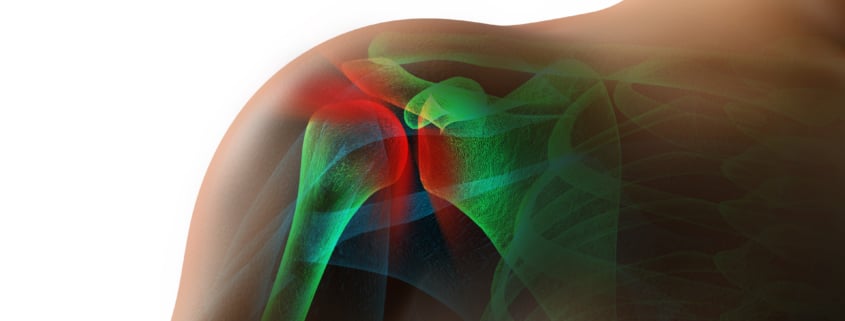

Cartilage is a flexible tissue that exists at the end of your bones at joints and also exists in other parts of your body such as your ears and nose. Cartilage allows the bones at joints to move against each other easily without causing pain.

When you have a cartilage defect, it causes bones at joints to hurt because of the cartilage rub against each other. The most common symptoms people with cartilage defects experience are stiffness, swelling, and inflammation in the joints. Although the actual defect is in the cartilage between the bones, the pain is caused by the bones rubbing against each other without adequate cushioning. The pain will likely radiate to the area surrounding the bones – especially if the condition goes untreated for an extended period of time.